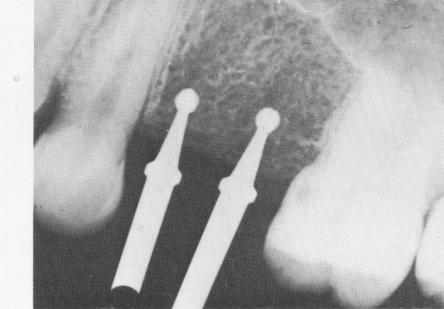

Fig. 8-11. A periapical intraoral radiograph showing 1 No. 6 round burs drilled into the edentulous bone.

1 Radiograph showing No. 6 implant round burs drilled into bone